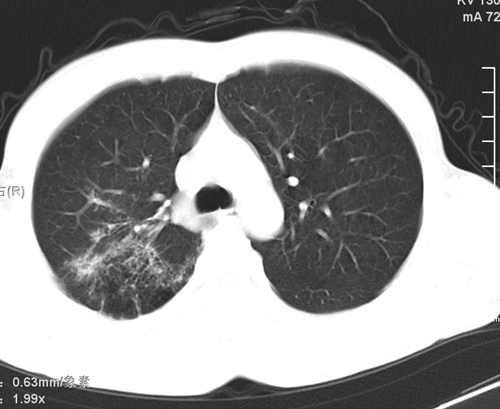

标题: CT24548:男 31 咳嗽 咯血一天 行CT检查 [打印本页]

标题: CT24548:男 31 咳嗽 咯血一天 行CT检查

ct考虑结核 但化验结果示白细胞总数 淋巴均正常,血沉7mm/h不快,请看看结核 支扩还是其他

右肺上叶尖端,后段下叶背段结核伴空洞形成

继发性肺结核伴空洞形成!

右肺继发性肺结核伴空洞形成!

好发部位+多种性质病灶=典型tb